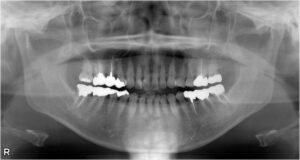

大臼歯2本欠損症例

BEFORE AFTER 43歳女性/上下2本欠損/インプラント埋込手術 【治療内容】 右上第二大臼歯の被せ物が外れてし…